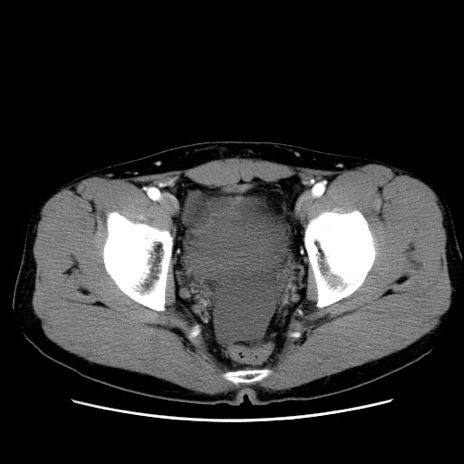

症例36(横断像)

【症例】20歳代 男性

【主訴】心窩部痛

【現病歴】今朝より上腹部痛あり。一旦軽快していたが再度出現したため救急要請。昨日夕に白身の魚を含む刺身を食べた。

【身体所見】BP 136/89mmHg、HR 74/min、BT 37.0℃、腹部:膨満、軟、心窩部に圧痛あり。反跳痛なし、筋性防御なし、腸雑音やや亢進あり。

【データ】WBC 17700、CRP 0.48